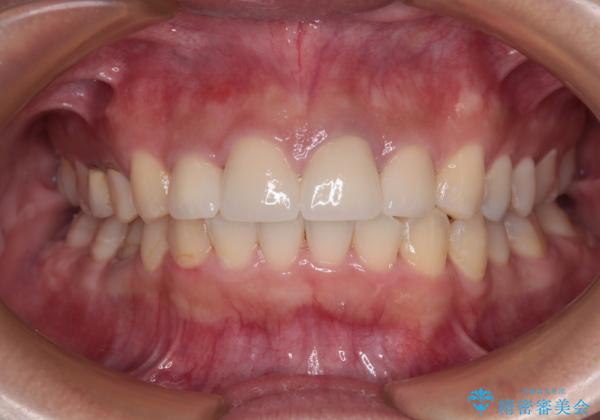

歯列から飛び出た歯 ワイヤー矯正で整った歯列に

- 下顎の歯列から飛び出した小臼歯を気にして来院された患者様です。

歯列以外に、上顎左右側切歯が矮小歯であり、上顎4前歯は失活していたため、矯正治療で歯列を整えるとともに上顎前歯の幅を調整し、矯正治療後にオールセラミッククラウンにて審美歯科治療を行うこととしました。

口元の印象が大きく改善し、患者様には大変満足していただけました。